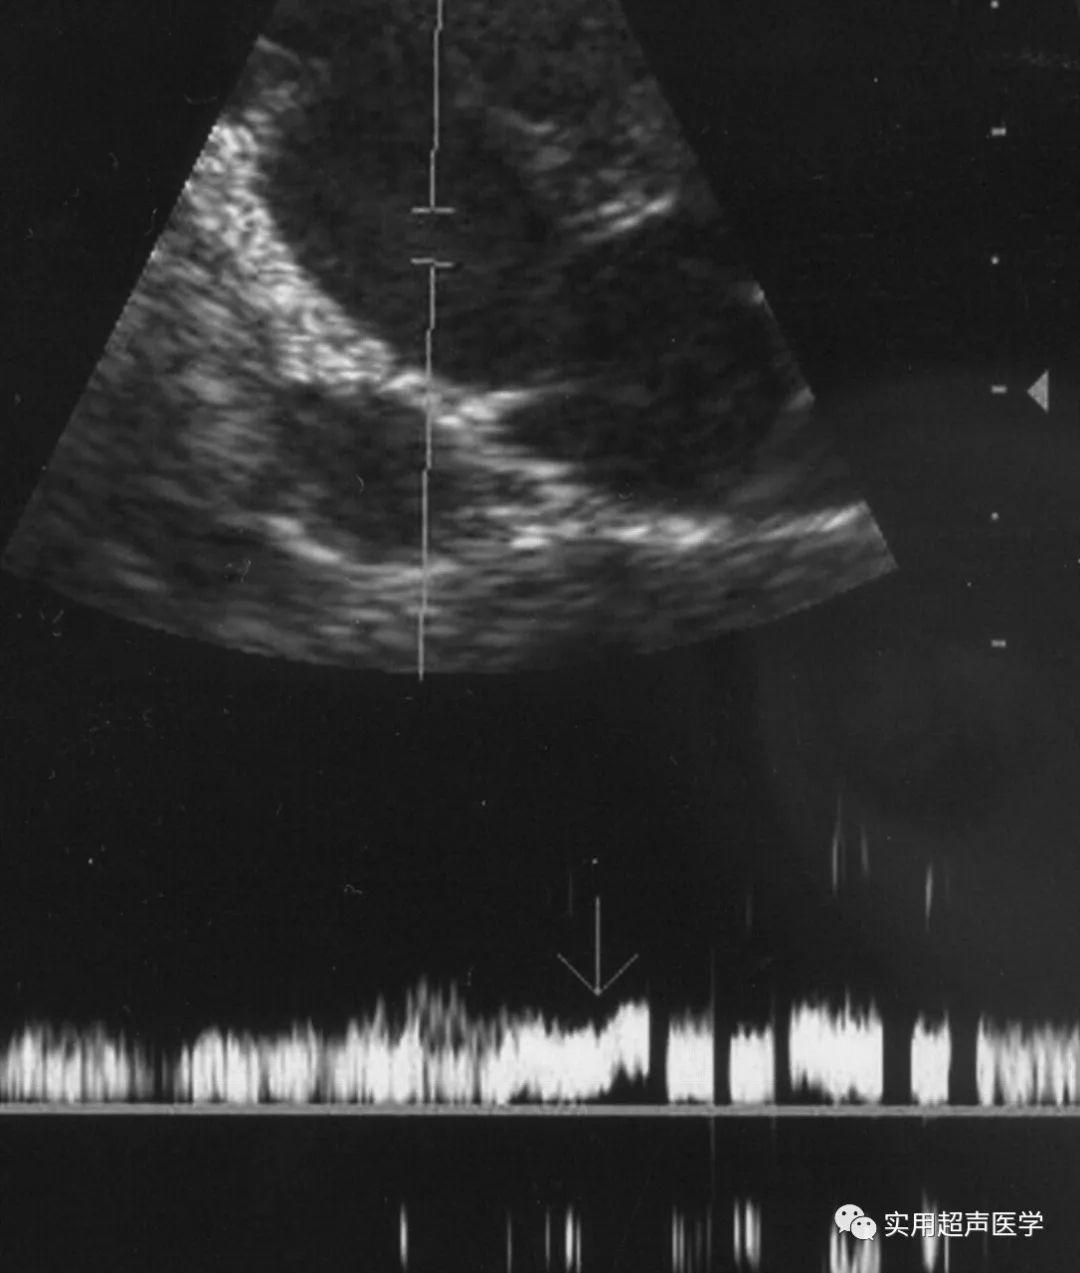

47岁女性盆腔充血综合征患者。扩张型卵巢静脉丛的多普勒超声图显示,Valsalva 操作显示血流方向逆转,与选择性卵巢静脉造影显示的反流相关(未显示)。

39岁盆腔充血综合征女性患者。扩张卵巢静脉丛的多普勒超声检查显示血流突然消失,与选择性卵巢静脉造影显示淤滞相关(未显示)。

最近的一份报告表明,Valsalva手术期间盆腔精索静脉曲张的初始加重是诊断盆腔充血综合征的重要多普勒超声检查发现,类似于男性阴囊精索静脉曲张的诊断方法。在男性中,Valsalva操作期间扩张静脉的初始血流增压对于诊断阴囊精索静脉曲张很重要。由于阴囊精索静脉曲张位于腹膜腔外,如果 Valsalva 操作期间腹膜压力升高,阴囊精索静脉曲张中的突然血流充盈会使多普勒超声检查显示初始血流增强。由于女性的盆腔精索静脉曲张是腹腔内的,因此在盆腔充血综合征患者的Valsalva操作过程中会出现可变的多普勒波形。在Valsalva操作过程中,扩张盆腔静脉中多普勒波形的可变变化,包括初始增强,流型无变化,流向逆转和血流突然消失。多普勒超声检查显示的血流方向逆转和突然消失分别与选择性卵巢静脉造影的反流和淤滞相关。